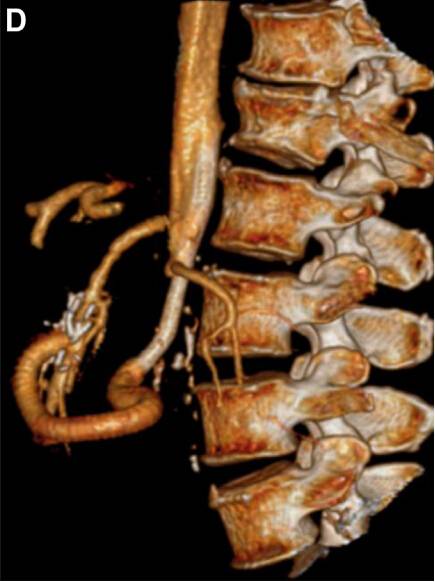

术后 CT 显示置入的血管清晰可见,且肠系膜上动脉充盈(图 C 和 D)。

图 C、D. 术后 CT 显示置入的血管清晰可见,且肠系膜上动脉充盈